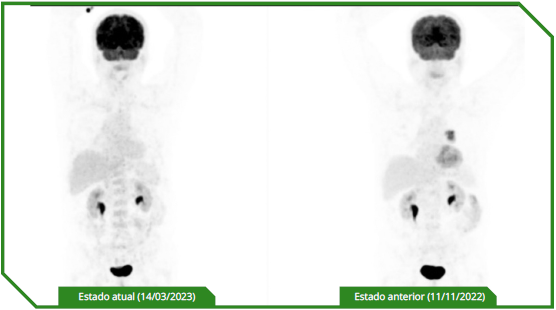

Paciente masculino de 65 anos, previamente sem comorbidades, diagnosticado com carcinoma espinocelular de língua, tratado inicialmente com cirurgia e radioterapia adjuvante, evoluindo precocemente com doença metastática pulmonar e óssea. No momento da avaliação oncológica, apresentava performance status comprometido e alta expressão de PD‑L1 (CPS 30). Optou-se por imunoterapia isolada em primeira linha, considerando perfil clínico e objetivo de redução de toxicidade, com acompanhamento longitudinal e intervenções locais conforme necessidade.